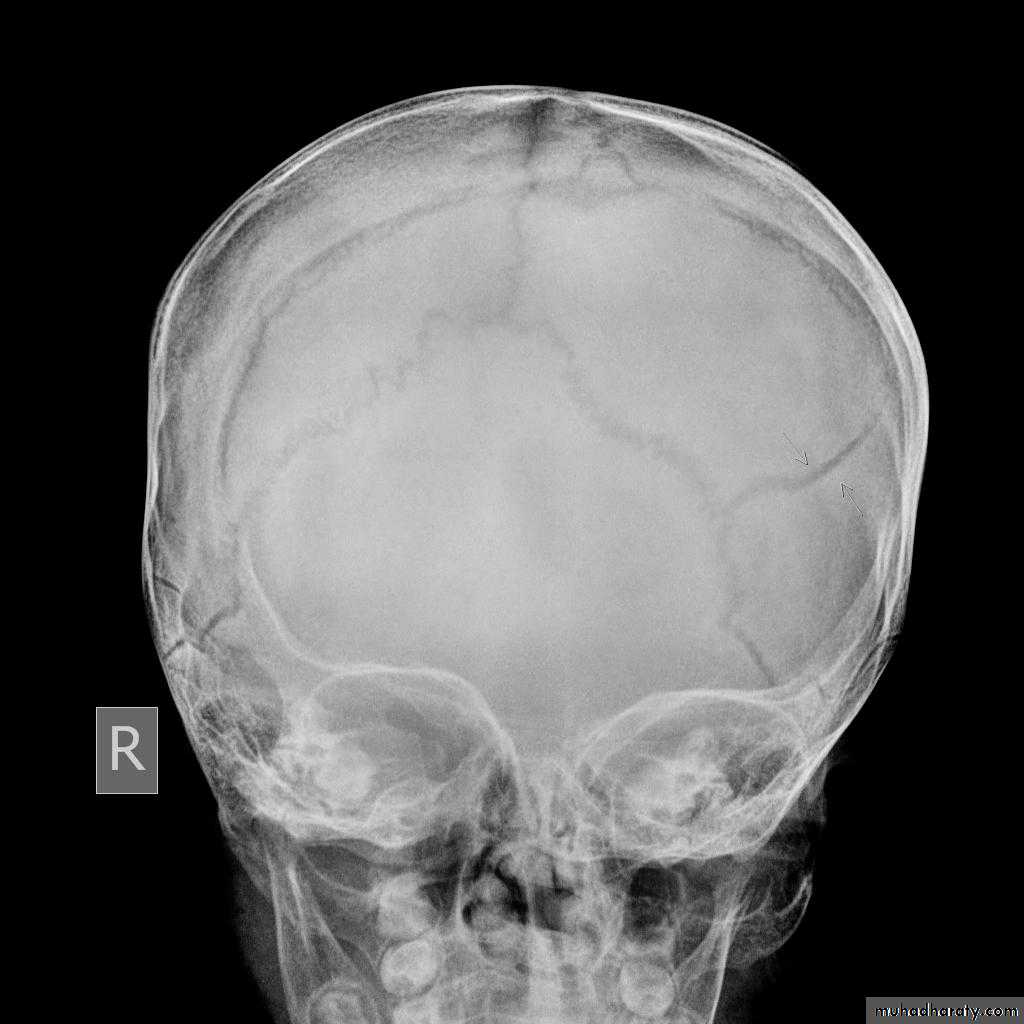

Skull X-rayBony configuration and shape

Bone densityAny Lytic lesion

Any fracture

Any calcification

Diploë, pituitary fossa, paranasal sinuses, orbits

The sutures